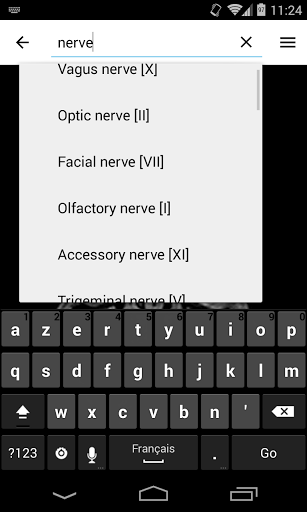

*Improving performance of anatomical structure search

*Find your anatomical parts more easily thanks to the new, more intuitive and powerful search feature